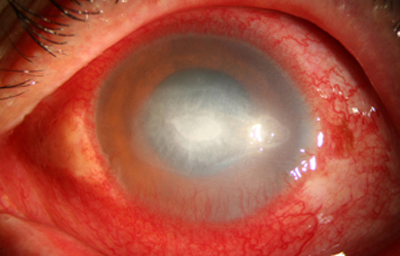

Superficie corneal irregular y grisácea, (Fig. 1, 2) con opácidades granulares en parche y formación de líneas epiteliales elevadas de aspecto granular (Fig. 3), que pueden arborizar dando imágenes de pseudodendritas. Opacidades superficiales satélites. (Figura 4) Inyección ciliar. Ulceración epitelial variante. (Figura 5).

Acanthamoeba Síntomas de 15 días evolución

Fig. 1 Síntomas de 15 días evolución